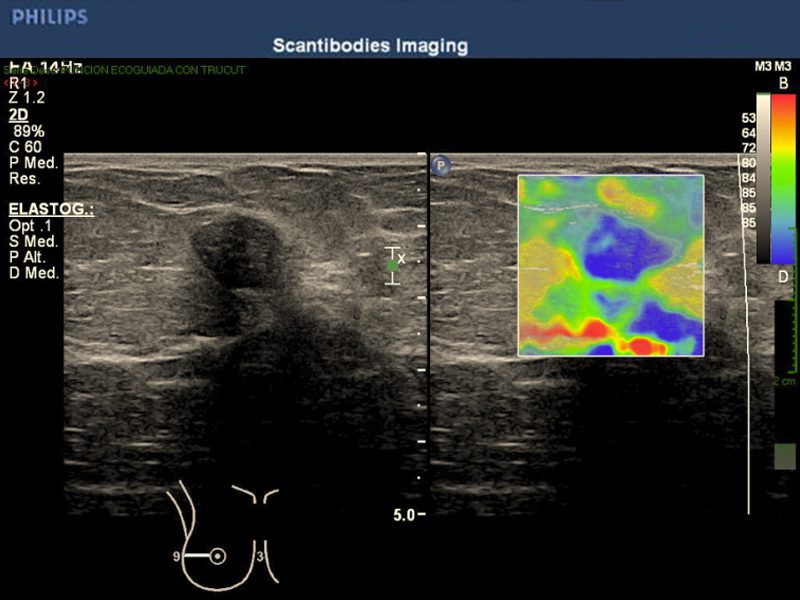

El ultrasonido iU22 xMatrix es un sistema que provee imágenes nítidas de alta resolución, y calidad única en 2D, 3D Y 4D de un mismo transductor. Provee una perspectiva clara durante las biopsias y ablaciones. El equipo tiene la capacidad de realizar el estudio de elastografía mamaria.

Elastografía por ultrasonido